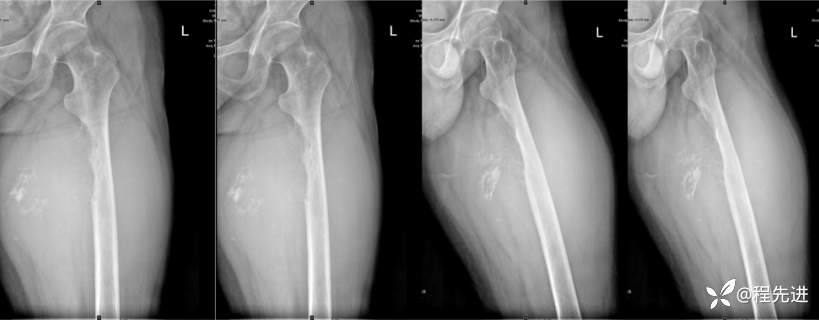

DR